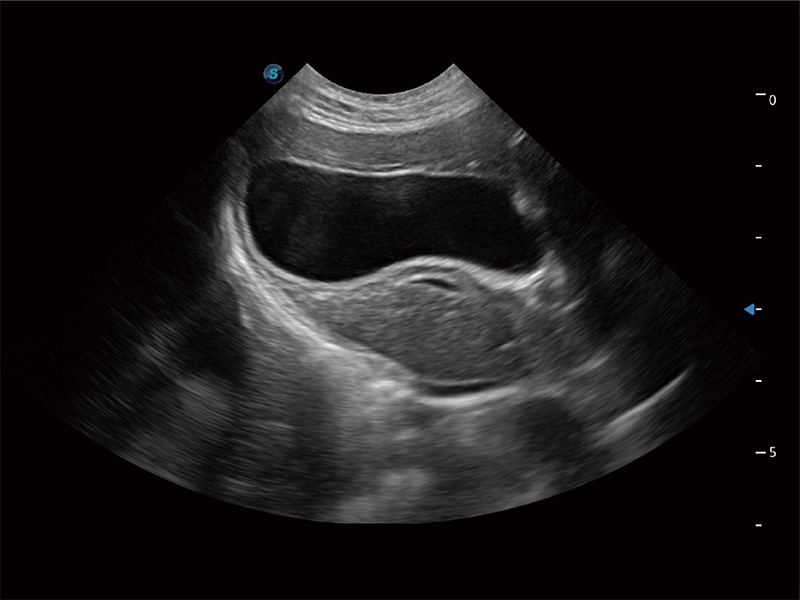

动物是人类最亲密的朋友和最值得信赖的伙伴。九州酷游也一直致力于探索动物专用的超声影像解决方案。全新推出的ProPet系列,是九州酷游在动物超声影像智能化、专业化、精准化的一次跨越式革新。动物不能用言语来表述自己的不适,通过超声影像,ProPet系列搭建了动物医生与不同物种沟通的“桥梁”,为动物医生注入了“治愈之力”。 ProPet 80 是九州酷游匠心打造的一款高端动物专用彩超,采用性能卓越的全新硬件架构,极大提升超声系统的运行效率和数据处理能力,帮助动物医生从容应对日益增多的挑战性病例和日益多样化的临床需求。

高性能和先进的临床应用工具可以为动物医生提供临床信心。ProPet 80 搭载了先进的腹部和浅表应用工具,帮助医生在日常临床实践中发挥前所未有的作用。

ProPet 80 专为动物医生设计,对不同的动物体型和生理结构作出了针对性的优化。通过动物影像专用软件,可满足个性化的应用需求,帮助动物医生获得更精确的诊断数据。

为精细结构及组织边缘提供高清晰度的图像和更大的成像视野。帮助减轻医生的用眼疲劳,快速精准获得测量的数据。